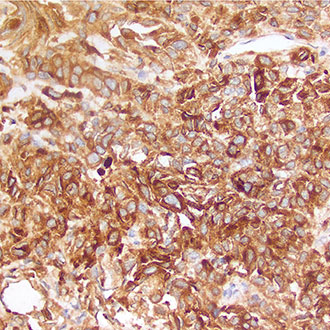

E-Cadherin

E-Cadherin -